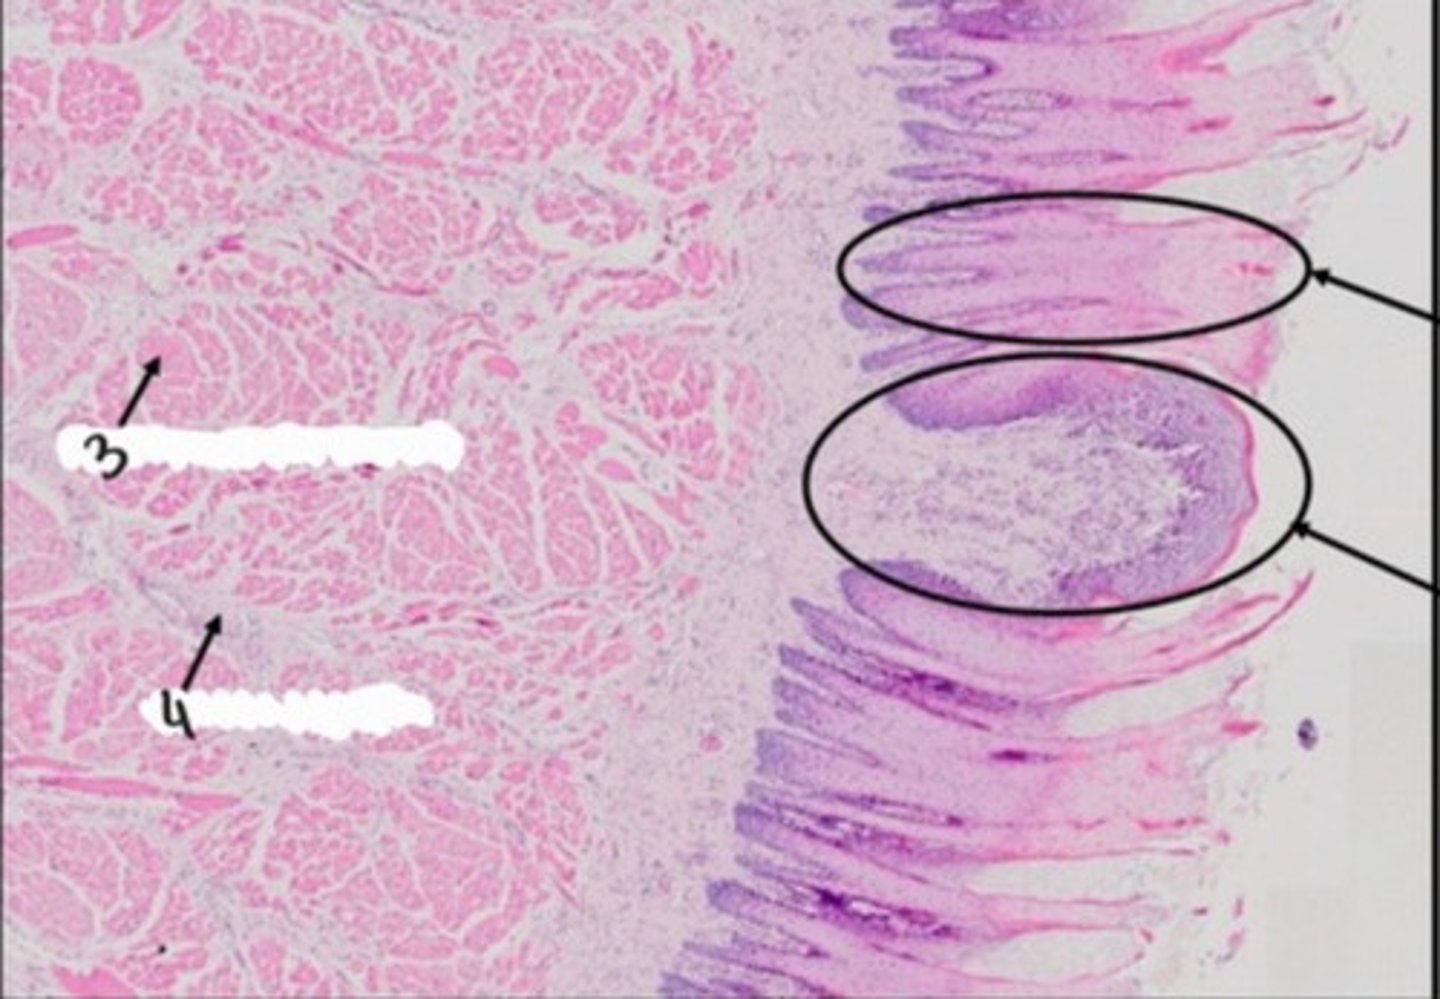

Język - migdałek językowy (H+E)

Wyrostek robaczkowy (H+E)